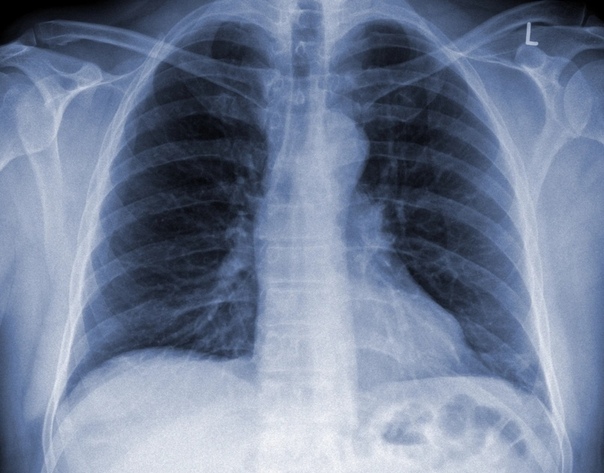

Сергей Авдеев: Да, безусловно. Сегодня большой акцент делается на компьютерной томографии легких. Этот метод относится к имидж-диагностике, как и рентгенография. Но компьютерная томография — более точная и специфичная методика выявления изменений в ткани легких по сравнению с обычной рентгенографией. Большинству пациентов с COVID-19 как раз и требуется такая методика. Компьютерную томографию я бы поставил сегодня на первое место среди всех имеющихся методов для подтверждения диагноза. По своей чувствительности она даже превосходит лабораторную диагностику для подтверждения вирусной инфекции. Чувствительность компьютерной томографии превышает 90%.

Сергей Авдеев: Да, отличия существенные. При COVID-19 практически всегда пневмония двусторонняя, расположена по периферии легких (под плевральной оболочкой). На начальных этапах она имеет вид, как говорят рентгенологи, «матового стекла». При прогрессировании изменения становятся более плотными и распространенными. А затем происходит фаза обратного развития — уменьшение размера и плотности легочных инфильтратов.

Да, это одна из особенностей COVID-19. Самый действенный метод — увидеть пневмонию на компьютерной томографии. Чувствительность метода КТ достигает 97 процентов, поэтому он выходит на первый план при диагностике воспалительного процесса.

Если коротко, то при COVID-19 пневмония — двусторонняя, локализация — периферическая. Микоплазменные пневмонии чаще односторонние. Встречаются и двусторонние, однако в этом случае томографические снимки отличаются, изменения в легких иные.

Наши рентгенологи, описывая снимки легких при ковидных пневмониях, употребляют такие термины, как «булыжная мостовая», симптом «матового стекла». Именно так выглядят поражения

На раннем этапе заболевания, по словам врача, определить вирусную пневмонию можно только с помощью компьютерной томографии. Но если процесс уже достаточно распространен, врачи могут распознать вирусное воспаление легких и с помощью рентгенографии.

КТ на ранней стадии позволяет увидеть те изменения, которые называются синдромом «матового стекла». На снимке видно, что альвеолы как бы затянуты «дымкой». Если бактериальная пневмония проявляется в виде участков уплотнения, очаговых теней, то здесь легкая «дымка» окутывает все ткани альвеол.

Более тяжелые стадии вирусной пневмонии на рентгеновском снимке напоминают, по словам специалиста, «булыжную мостовую».